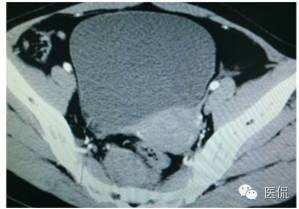

CT平扫(CT值23HU)